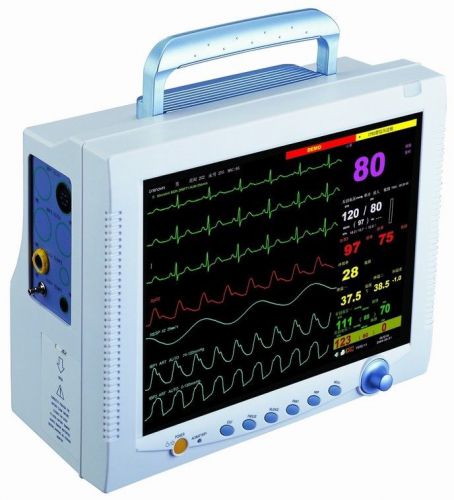

Mindray PM-9000VET Vital Signs Monitor

BIOLIGHT BLT M9000 VET VETERINARY MONITOR WITH CO2 CARBON DIOXIDE NEW ,USA

CE FDA Vet veterinary Animal 8.4inch Patient Monitor 6 parameter + WARRANTY V MO